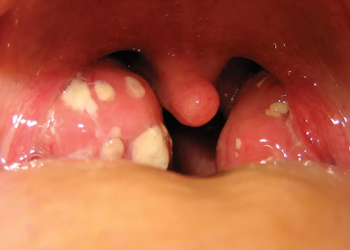

• High fever, swollen or pus-covered tonsils

Common causes include viral infections (e.g., cold, influenza), streptococcal bacteria, tonsillar stones, allergies, smoking, reflux and immunological factors. Examination, rapid testing and throat culture guide accurate diagnosis.